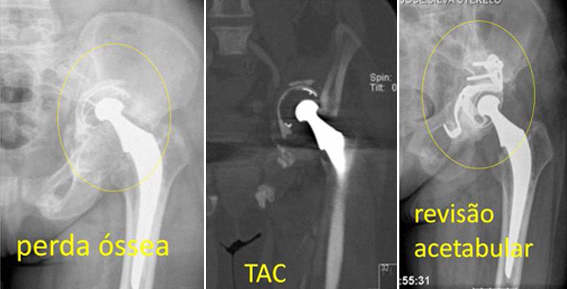

Em casos de osteólise simples e localizada, poderá ser evitada a revisão da prótese colocando enxerto ósseo no local da osteólise.